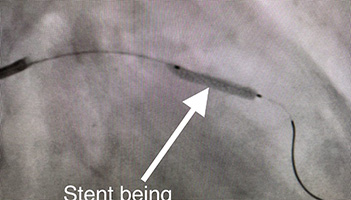

73 y/o female presents with accelerating symptoms of angina. Angiogram pictures show Left Anterior Descending artery (LAD) is severely blocked(stenosed). She receives an initial balloon dilatation and finally a drug eluting stent is implanted (see final result). She no longer has chest pain.